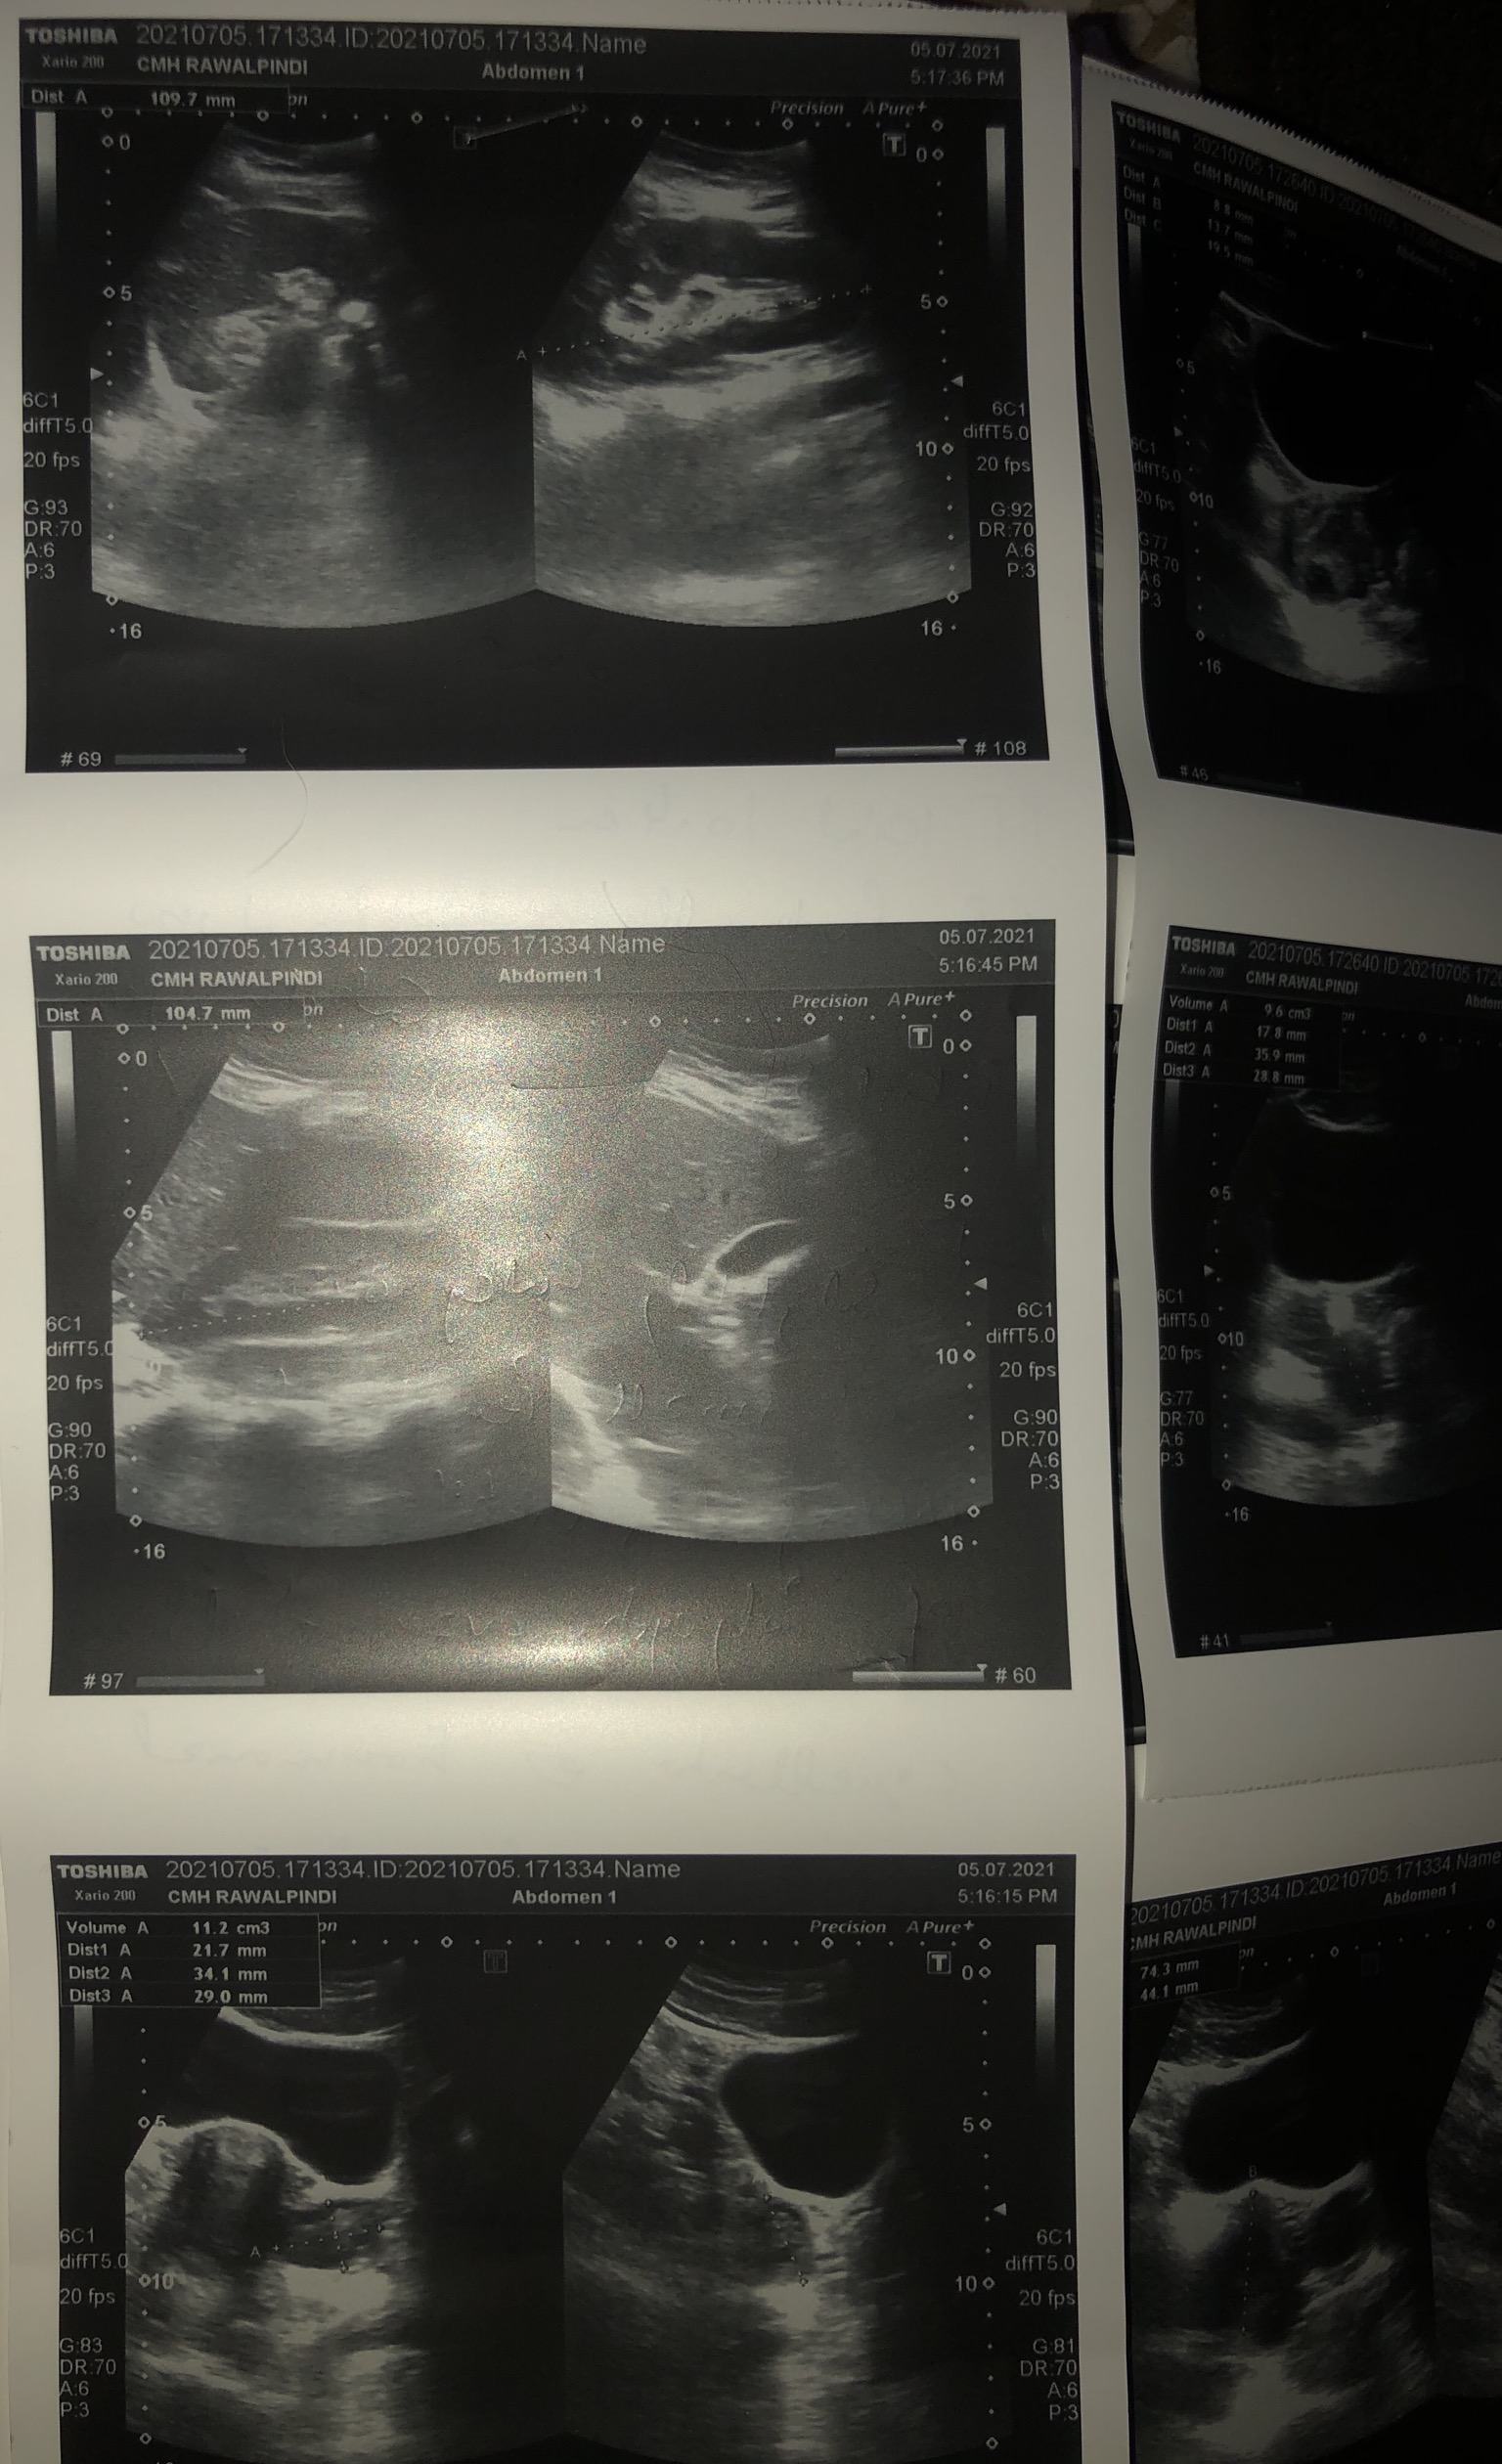

Unmarried facing periods issue for last 5 to 6 months Delayed and very less flow brownish discharge Please helo me read usg report and suggest treatment plzz

You seem to be suffering from polycystic ovarian syndrome.

Please seek consultation for detailed advice